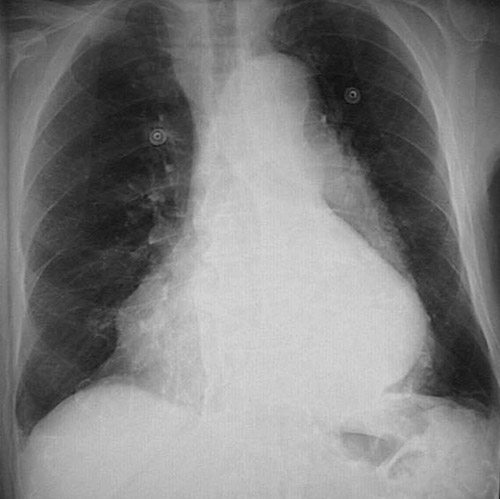

This chest radiograph demonstrates marked cardiomegaly, with the left heart edge appearing far to the left.